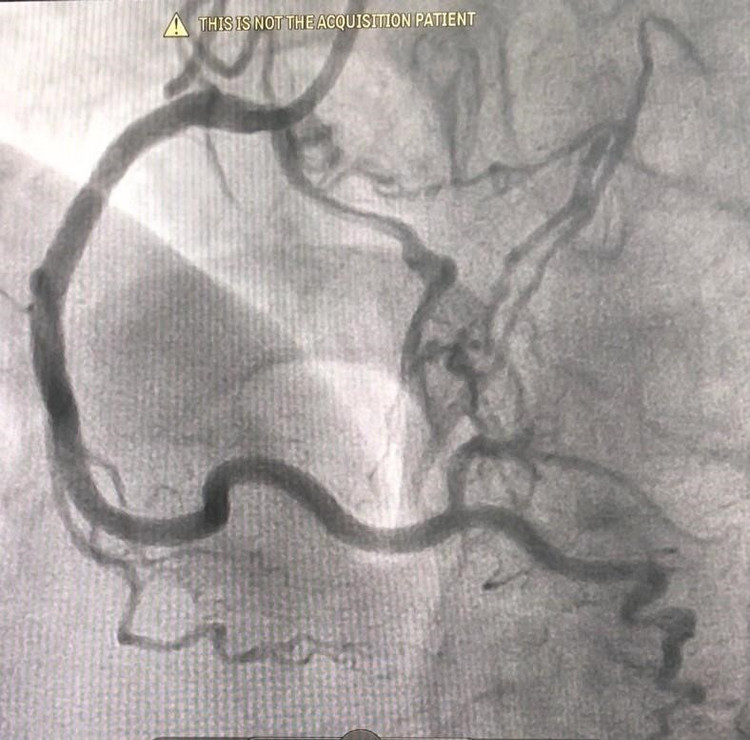

Sau khi hội chẩn, các bác sĩ Khoa Can thiệp Tim và mạch máu đã thống nhất tiến hành can thiệp đặt stent động mạch vành cho người bệnh. Sau 2 lần thực hiện phương pháp can thiệp động mạch vành, các bác sĩ đã tái thông và đặt stent 2 nhánh mạch lớn là động mạch vành phải và động mạch mũ bên trái. Sau can thiệp 5 ngày tình trạng của người bệnh ổn định, có thể tự đi bộ, leo cầu thang và không còn những cơn đau ngực khi gắng sức. Người bệnh đã được xuất viện và tái khám định kỳ.

| Động mạch vành phải sau can thiệp đặt stent Động mạch mũ sau can thiệp đặt stent |